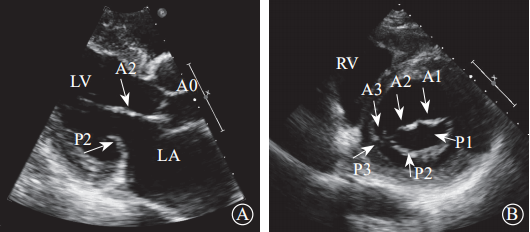

通过采集以下切面显示二尖瓣瓣叶各扇叶。(1)胸骨旁左心室长轴切面,显示A2、P2(图5A);(2)二尖瓣水平短轴切面,显示整个前后叶(图5B);(3)心尖四腔心切面,显示A2、P2(图6A);(4)心尖长轴切面,显示A2、P2(图6B);(5)心尖二腔心切面,显示A1、P3(图7A);(6)心尖二尖瓣交界处长轴切面,显示P1、A2、P3(图7B)。经胸超声心动图通过上述切面评价MR的机制、程度以及部位,并确定瓣膜运动异常的扇叶。

图 5 经胸二维超声心动图显示二尖瓣瓣叶各扇叶 A. 胸骨旁长轴切面,显示二尖瓣前叶 A2 处、二尖瓣后叶 P2 处;B.二尖瓣水平短轴切面,显示二尖瓣前叶 A1、A2、A3 及二尖瓣后叶 P1、P2、P3

注:LA,左心房;LV,左心室;RA,右心房;RV,右心室

图 6 经胸二维超声心动图显示二尖瓣瓣叶各扇叶 A. 心尖四腔心切面,显示二尖瓣前叶 A2 处、二尖瓣后叶 P2 处;B.心尖长轴切面,显示二尖瓣前叶 A2 处、二尖瓣后叶 P2 处

注:LA,左心房;LV,左心室

图 7 经胸二维超声心动图显示二尖瓣瓣叶各扇叶 A. 心尖二腔心切面,显示二尖瓣前叶 A1处、二尖瓣后叶 P3 处;B.二尖瓣交界处长轴切面,显示二尖瓣后叶 P1、前叶 A2、后叶 P3